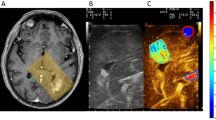

All experiments were performed on male Sprague Dawley rats. The rats were placed on an MRI Guided Focused Ultrasound (MRgFUS) transducer (Exablate Model 4000 Type-2 system, Fig. 1a), which was then placed in the MRI, and treatment planning images were acquired to define the treatment area (Fig. 1b, see “Methods” for details).

a MRgFUS semi-hemisphere transducer (diameter: 30 cm, 1024 elements) with a specially designed holder on top of the transducer and rat inside. The magnetic resonance receiving coil was placed on top of rat’s head area. Two passive cavitation detectors captured the emitted pressure waves from microbubble activities. b T2-weighted planning images with target locations. The targets covered the right hemisphere (not including the cerebellum) and contained 15–18 sub-spots with a distance of 2 mm between sub-spot centers.

a Pre- and post-treatment R2* maps (left) and ΔR2* map, with and without a treatment mask (right). The white marks in the post-treatment R2* map (indicated by arrows) and the red marks in ΔR2* maps indicate the treatment-related changes. b Pre- and post-treatment R1 maps (left) and Gd-liposomal concentration map (right); arrows indicate liposome presence. c ΔR2* map with treatment area mask, after registration to the Gd-liposomal concentration map orientation (left). ΔR2* map after diffusion mimicking registration to the liposome concentration map (middle); note the ΔR2* distribution radial expansion. Gd-liposomal concentration map with treatment area mask (right).

a Qualitative observation without registration alignment of different liposome populations’ Gd signal (T1-weighted imaging, left, white areas) and its treatment-related qualitative R2* changes (T2-weighted imaging, right, dark areas); although no registration was performed, it noticeable that the liposome location correlated with the local R2* changes. b 44-nm liposomes presence inside the brain parenchyma over a period of 1 month. T1-weighted imaging parameters: FSE, TR: 500 ms, TE: 22 ms, ET: 4. T2-weighted imaging parameters: GRE, TR: 620 ms, TE: 38 ms; slice thickness: 2 mm, FOV: 18 cm, grid resolution: 224 × 224 were same for both the T1- and T2-weighted images.